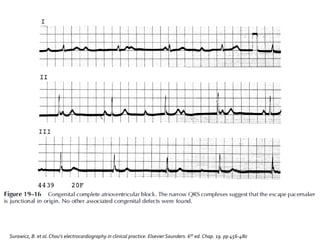

 Ninguna onda P conduce hacia los ventrículos

 El ECG muestra disociaciónAV

 Intervalos PP que no coinciden con los intervalos

RR

 Actividad auricular independiente de la ventricular

Ondas P y

complejos QRS

disociados

Cada uno a su

ritmo de

marcapaso

Relación P-R

cambiante

constantemente

Ondas P a través

de todo el ciclo

ventricular

Ritmo atrial

siempre mayor

al ventricular

Causas más

comunes

Enfermedad de

Lev

• Calcificacióndel

sistema de conducción

Lenegre

• Cambios

esclerodegenerativos

Producen bloqueo

de rama bilateral.